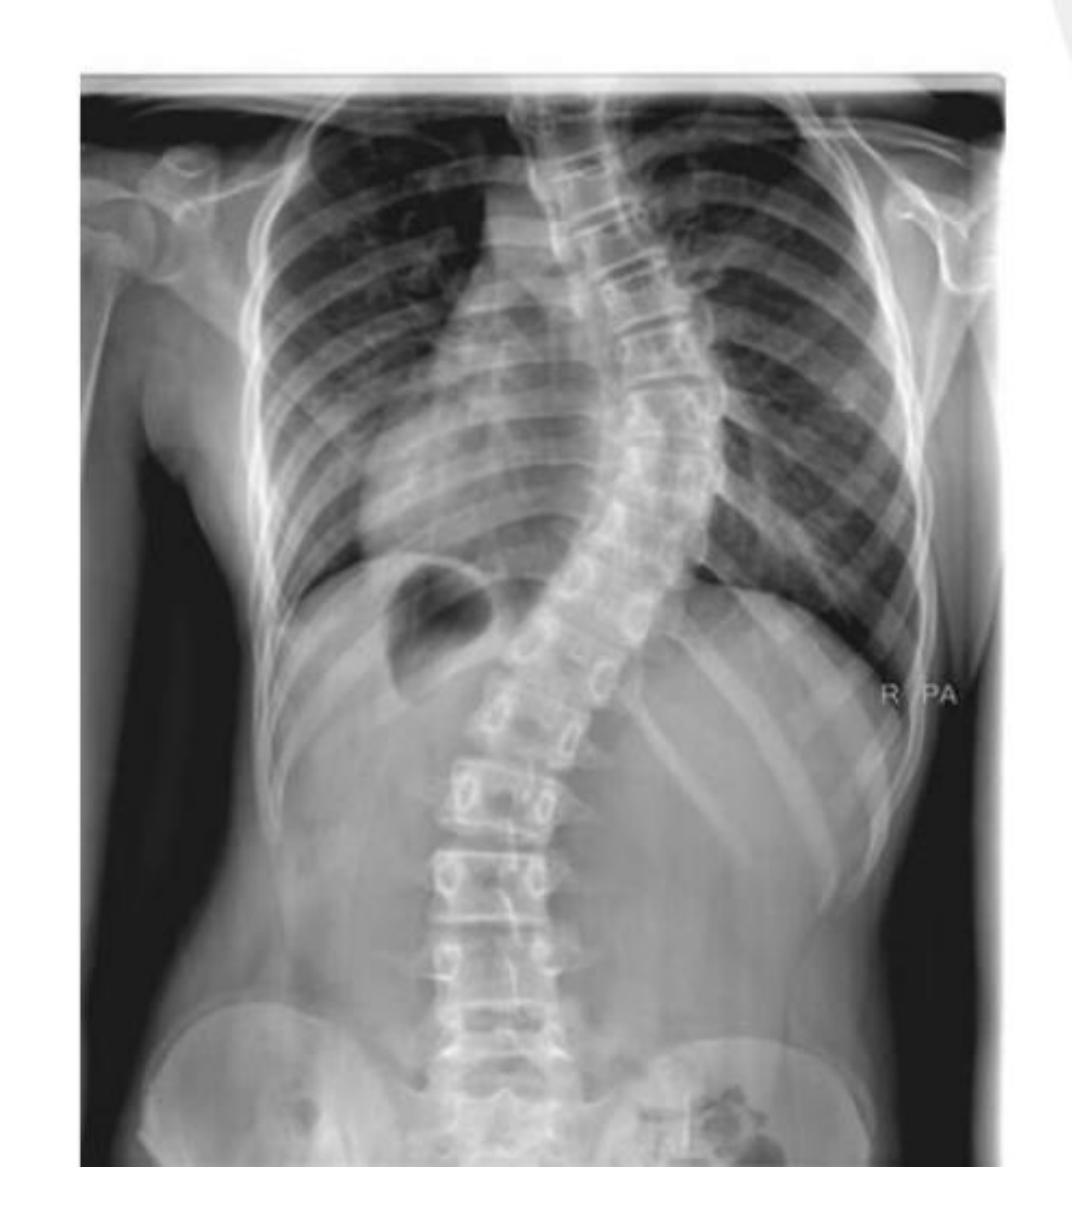

Which of the following is associated with this finding?

- Adolescent Idiopathic Scoliosis

A 14-year-old girl presented to the clinic after her parents noticed a deformity in her back. Adamโs test was positive. Which of the following pathologies represents this case?

- Idiopathic scoliosis